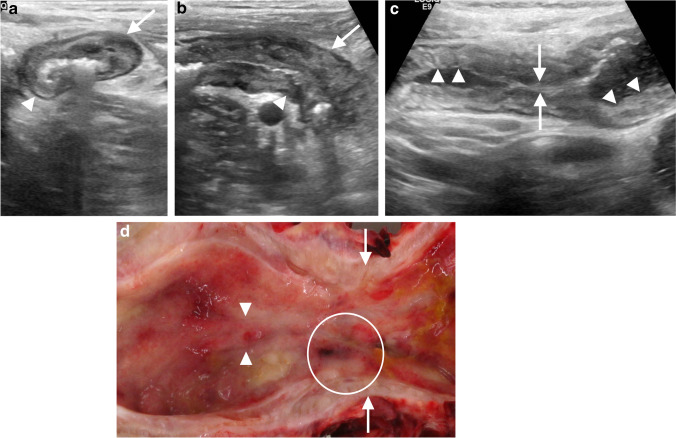

The hallmark of active Crohn disease on US is bowel wall thickening and hypervascularity predominantly affecting the submucosa. Asymmetrical mural thickening along the mesenteric side of bowel has been cited as a fairly specific feature of Crohn disease, with less common differential considerations for asymmetrical mural thickening including tuberculous and fungal enterocolitis, as well as malignancy [20]. The spatial resolution of US can nicely illustrate the transmural nature of the disease. Superficial ulceration interrupts the normally smooth echogenic mucosal interface, producing a cobblestone appearance (Fig. 4), while deeper involvement can result in linear hypoechoic intramural ulcers, serosal penetration with fistula or abscess formation, and stricture [6]. Loss of normal mural stratification is evident with prolonged or severe inflammation and has been correlated with deep ulceration and fissures on histopathology, as well as with need for surgical resection in some series [1, 21]. Such severely affected segments demonstrate fairly homogeneous hypoechogenicity across the mucosa, submucosa and muscularis propria (Fig. 5). In practice, mixed echo patterns often reflect the coexistence of inflammation and fibrosis within diseased bowel segments.

Fig. 4.

Penetrating and stricturing Crohn disease manifesting as chronic obstructive symptoms in a 14-year-old boy. He ultimately required ileocecectomy for localized perforation. a, b Transverse (a) and sagittal (b) gray-scale US images of the terminal ileum demonstrate asymmetrical mural thickening, more pronounced along the mesenteric side of the bowel (arrow) than the non-mesenteric side (arrowhead). c Sagittal gray-scale US of the upstream ileum shows irregular contour of the mucosal interface, or cobblestoning (arrowheads), reflecting mucosal ulceration, as well as a short segment of luminal narrowing (arrows). d Gross specimen photo of longitudinally cut small-bowel with the mucosa exposed shows linear ulceration/fissuring (arrowheads) and uneven, bumpy mucosal contour (circle) reflecting cobblestoning, as well as luminal narrowing (arrows)